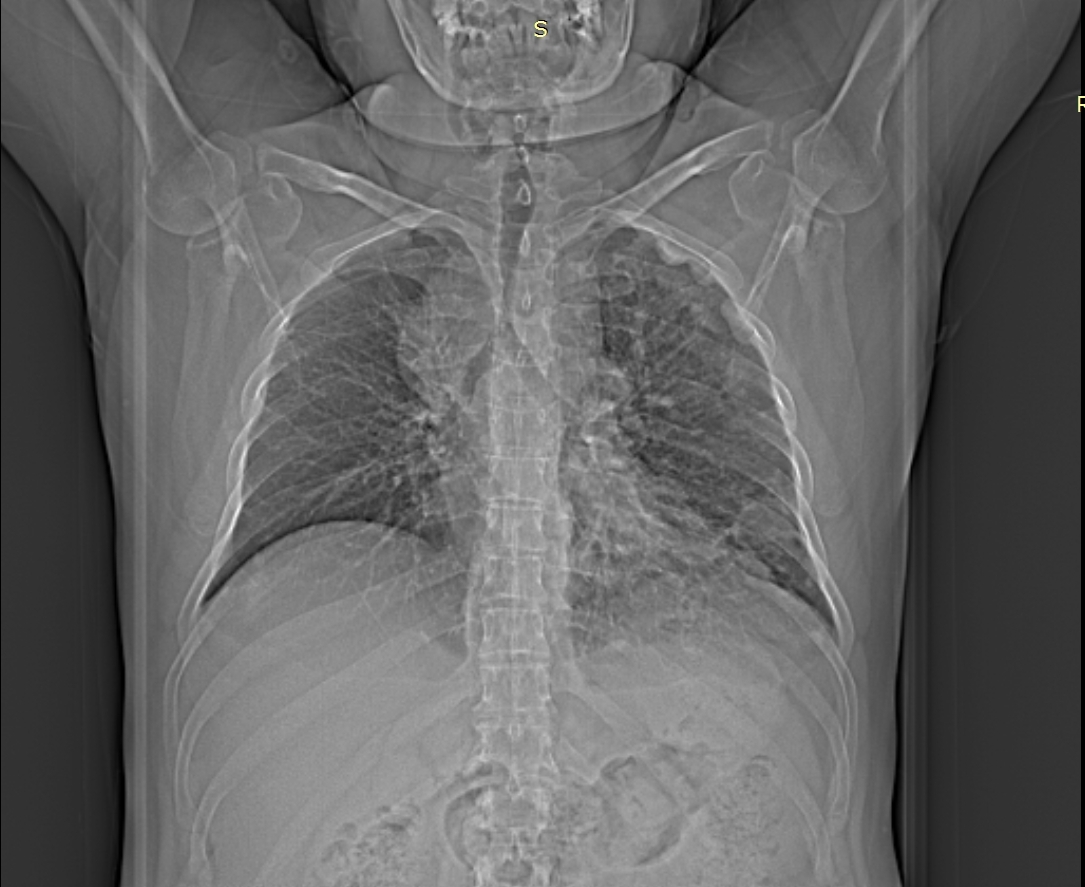

პაციენტი, 41 წლის მამაკაცი, 2015 წლის ოქტომბერში დაესვა მარჯვენა ფილტვის ბრტყელუჯრედოვანი გაურქოვანებელი კარცინომის დიაგნოზი. მიუხედავად ქიმიოთერაპიისა და რადიაციული თერაპიისა, პაციენტის კლინიკო-ლაბორატორიული და რადიოლოგიური მონაცემები გაუარესდა. გაუჩნდა სტრიდორული სუნთქვა, მოხრჩობის შეგძნება, ძლიერი ქოშინი მოსვენებულ მდგომარეობაშიც. 2016 წლის 1 სექტემბრის კტ კვლევით ინახა ტრაქეის გარშემო მუფტასავით შემოხვეული გადიდებული ლიმფური კვანძების კონგლომერატი, რომლებიც კრიტიკულად ავიწროებენ ტრაქეის სანათურს. ქირურგების შეფასებით ტრაქეოსტომიული მილის ჩადგმა იყო შეუძლებელი. გადაწყდა სასიცოცხლო ჩვენებით ტრაქეის სტენტირება. პაციენტის დაინტუბირების შეუძლებლობის გამო მანიპულაცია ჩატარდა ადგილობრივი გაუტკივარებით. მანიპულაციამდე პაციენტს ჩაუტარდა სუნთქვითი ვარჯიში, რის შედეგადაც მან შესძლო სუნთქვის შეკავება 10 წმ-მდე ინდეფლატორით სტენტის გაშლის დროს. შედეგი იყო მყისიერი. პაციენტს გაუქრა სტრიდორი, სატურაცია აიწია 96-97%-მდე.